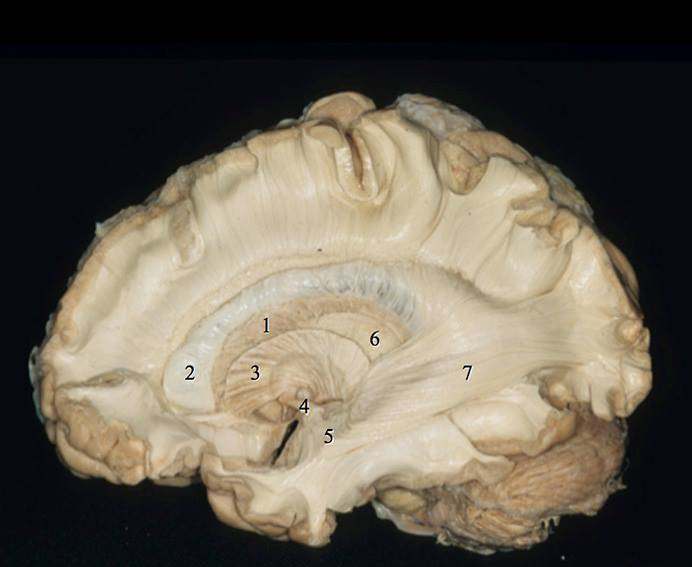

Várias estruturas anatômicas responsáveis por déficits neurológicos severos estão intimamente relacionadas com a cirurgia na ínsula, tais como lesões da artéria cerebral media e das áreas de linguagem no hemisfério dominante, por exemplo. A complexa anatomia do lobo da ínsula faz dessa região uma das de maior complexidade cirúrgica do corpo humano. Portanto, treinamento em laboratório de anatomia, estudo de material impresso em 3D, conhecimento de neurofisiologia intraoperatória e uso de equipamento neurocirúrgico moderno são fatores que influenciam os resultados cirúrgicos.

Leia mais em Anatomia Microcirúrgica Tridimensional Da Ínsula.